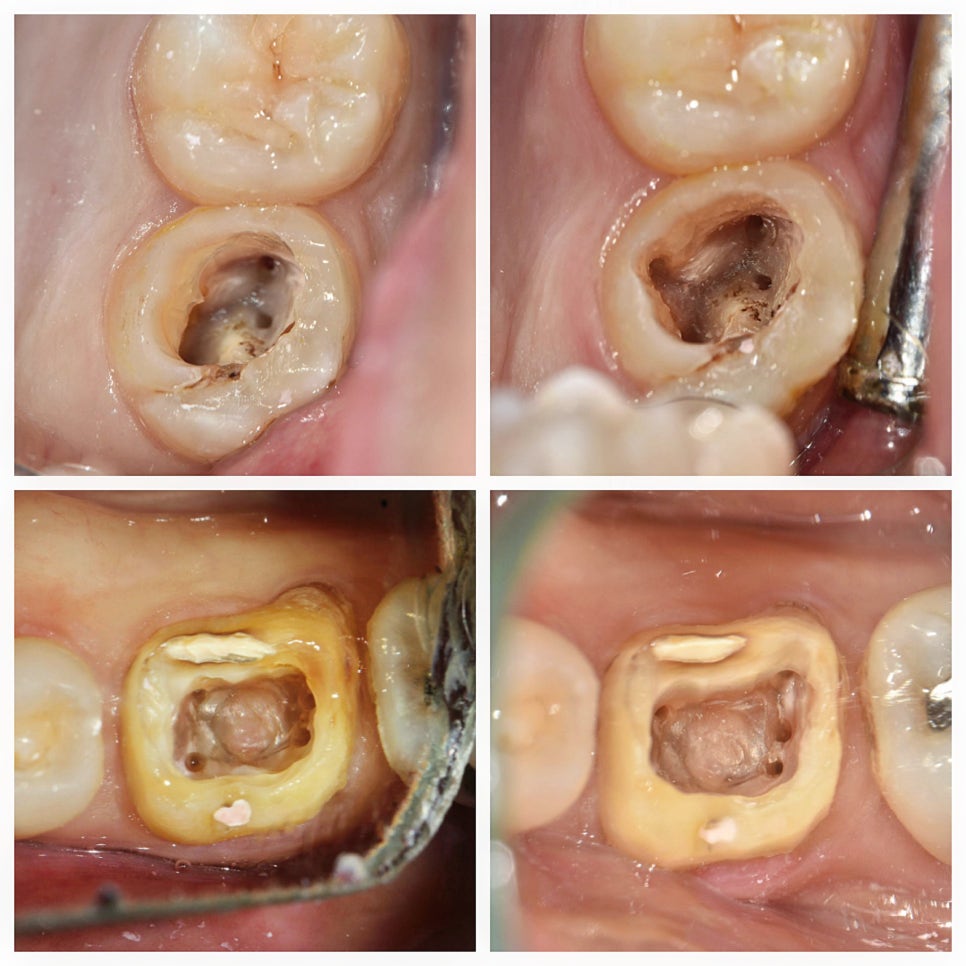

수요일 오후~야간 진료에는 오래간만에 근관치료가 재미있었는데, 역시 잘되면 재밌다ㅋㅋ 잘해야 재밌지 뭐든지🥰 아래는 지난주에 왠지 이상해서 DSLR로 와동 사진 찍어놨던 환자 두 분인데 두 분 모두 unusual 한 케이스였다. 상악 구개 2치근, 하악 원심 3근관 케이스를 만났다. 통상적인 근관 위치와 갯수를 생각하고 접근해서 다 찾았다고 생각했는데,

#17 팔라탈 2캐널 케이스 / #46 디스탈 3캐널 케이스

윗줄 사진 두 장은 블로그, 12주차 페닥일기에서 언급했던 상악 제2대구치 팔라탈치근 2개인 치아 임상사진이다. 예상했던 위치 근처에서 실제로 팔라탈 근관 하나를 더 찾았다.

그리고 아래 두 장은 블로그에 올리지는 않았었지만, 저번 주에 기존 크라운 벗겨낸(그래서 프렙이 돼있다) 하악 제1대구치. 디스탈 근관 2개 다 찾았는데 드러난 DL치근 위치가 너무 돌출되어 있어서 해당 위치에 근관이 하나 더 있을 것으로 예상했었다. 그래서 이번 주 예약에 엔도Z버로 확장해 보니 실제로 근관 하나가 더 나왔다. 사실 이 치아는 처음엔 근관 찾으려고 찍은 사진이 아니고, 크라운 벗기고 AO 하니까 와동 바닥에 타DC에서 퍼포 시켜놓고 리페어를 했는지 도대체 알 수가 없는 치질 아닌 웬 이상한 게 있어서 찍어놓은 것이다. 근데 이게 뭘까~ 하고 사진을 가만 보다 보니 갑자기 디스탈에 근관 하나 더 있을 것 같아서 체크해놨었던 케이스.

보통 하악 제1대구치가 5캐널이면 메지알에 MM캐널이 있어서 5캐널인데, 이거는 디스탈에 DM캐널이라고 해야되나, DB2라고 해야되나 아무튼 그게 있고 DL이 멀찌기 떨어져있는 증례였다. 간단히 논문 찾아보니 mandibular first molar에 middle distal canal 가지고 쓴 case report가 몇개 보이긴 하네.